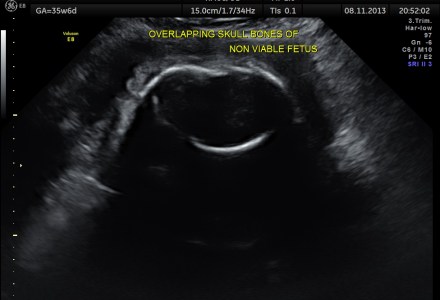

IUGR OR SKELETAL DYSPLASIA OR RENAL DYSPLASIA